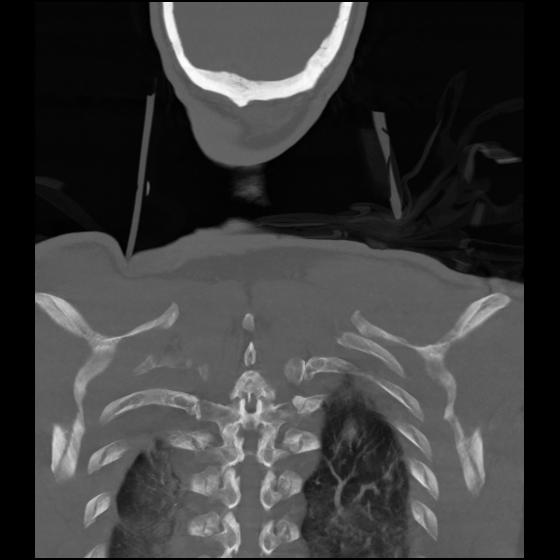

23 ANGIO,CE,Cor-MIP,5.000,ANGIO,Cor-MIP,